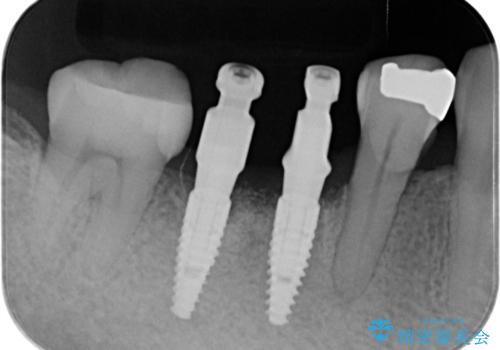

欠損部に1本だけインプラントを埋入しても大きな被せ物になってしまい清掃性が悪くなるので清掃性が良くなるように2本小臼歯用のインプラントを埋入しました。

- 抜歯、歯槽堤保存術・11万円 インプラント体、アバット、仮歯、ジルコニアクラウン・42.9万円×2 骨造成・5.5万円 e-maxインレー・7.7万円 費用は治療当時の料金となります